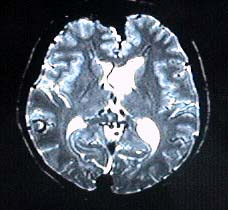

MRI T2WI image 40歳代後半の女性 2年前より右視力が低下し、最近はほとんど失明状態になった。

また、左眼の視力も低下してきた。

今回のMRI(T2強調画像)を示す。

この画像から考えられる疾患をあげなさい。